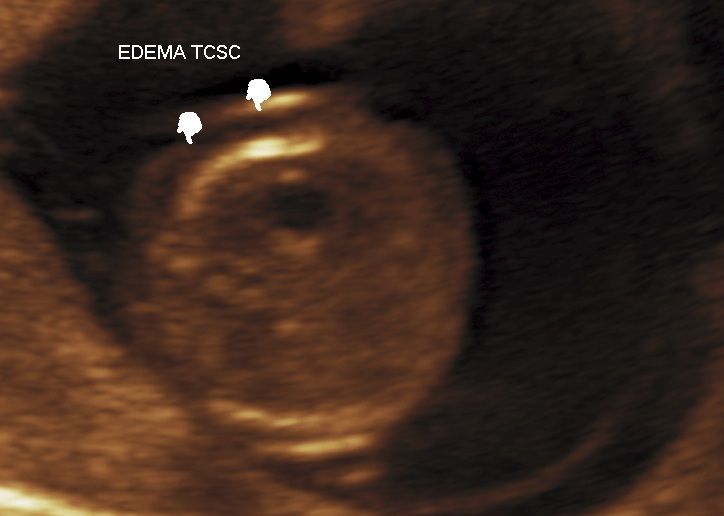

Realizamos las ecografías de viabilidad del embarazo, genética, morfológica, de bienestar fetal, ecocardiografías fetales, así como procedimientos invasivos como biopsia de vellosidades coriales y amniocentesis.